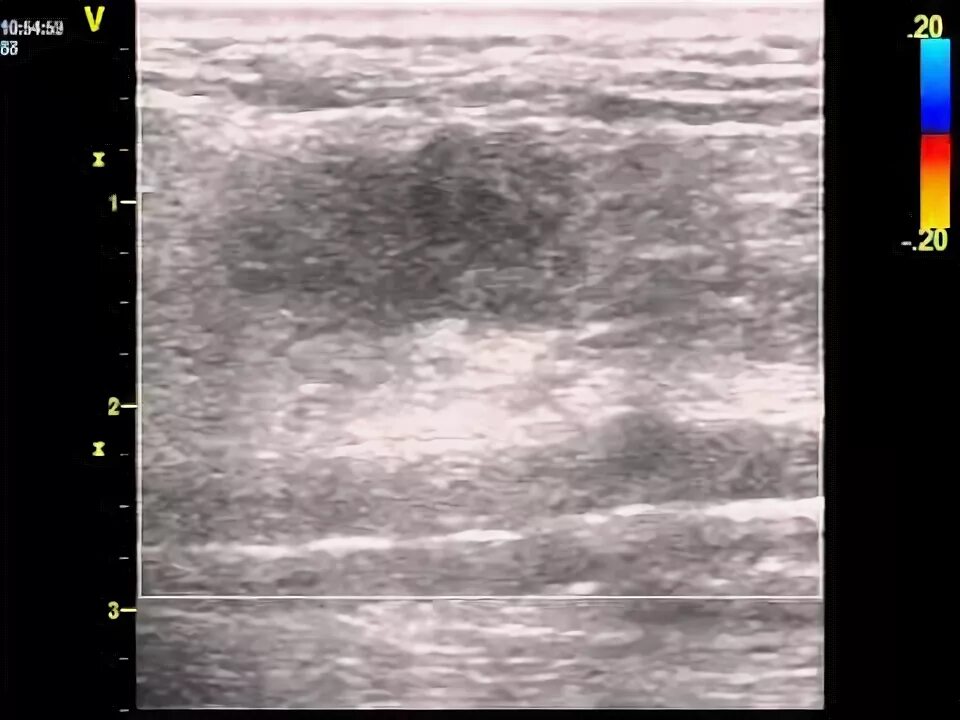

Фиброматоз мягких